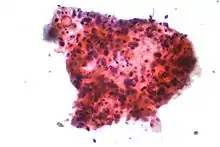

Ракові захворювання легень класифікують за гістологічним типом.[11] Ця класифікація має важливе значення для визначення лікування та прогнозування результатів захворювання. Переважна більшість ракових захворювань — це карциноми. Карцинома — це злоякісне новоутворення, що виникає з епітеліальних клітин. Карциноми легень класифікують за розміром і зовнішнім виглядом злоякісних клітин, виявлених лікарем-гістопатологом під мікроскопом. Загалом, карциноми легень бувають двох видів: недрібноклітинні та дрібноклітинні.[47]

Трьома основними типами недрібноклітинних карцином є аденокарцинома, плоскоклітинна карцинома та великоклітинна карцинома.[3]

Майже 40 % випадків раку легень — це аденокарциноми, що зазвичай виникають в периферичній легеневій тканині.[11] У більшості випадків виникнення аденокарцином пов'язане з палінням, однак серед людей, які викурили менше 100 сигарет у своєму житті (тобто ніколи або майже ніколи не палили),[3] аденокарцинома також є найбільш поширеною формою раку легень.[48] Серед жінок, які не палять, частіше зустрічається підтип аденокарциноми — бронхіолоальвеолярна карцинома, при якій показники виживання у довгостроковому періоді дуже високі.[49]

Плоскоклітинна карцинома виникає у 30 % випадків захворювання на рак легень. Як правило, вона утворюється поблизу великих дихальних шляхів. У центрі пухлини зазвичай утворюється порожнина, та виникає омертвіння клітин.[11] Близько 9 % випадків раку легень — це великоклітинна карцинома. Вона так називається, тому що ракові клітини великі за розміром, з надлишком цитоплазми, великими ядрами та помітними ядерцями.[11]